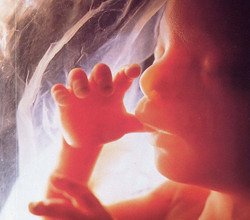

Развитие плода на 21 неделе беременности

Как уже говорилось, 21 неделю беременности можно считать определенным рубежом, ведь уже с конца этого срока ребенок способен сохранять жизнедеятельность вне материнской утробы.

Как уже говорилось, 21 неделю беременности можно считать определенным рубежом, ведь уже с конца этого срока ребенок способен сохранять жизнедеятельность вне материнской утробы.

Его внутренние органы уже полностью сформировались, начинается процесс отлаживания их функционирования и терморегуляции.

Кожа малыша больше не является красной, она порозовела и стала более плотной и гладкой, благодаря накопленной под кожей жировой клетчатке. Подкожный жир необходим для терморегуляции, чтобы плод мог сохранять внутреннее тепло.